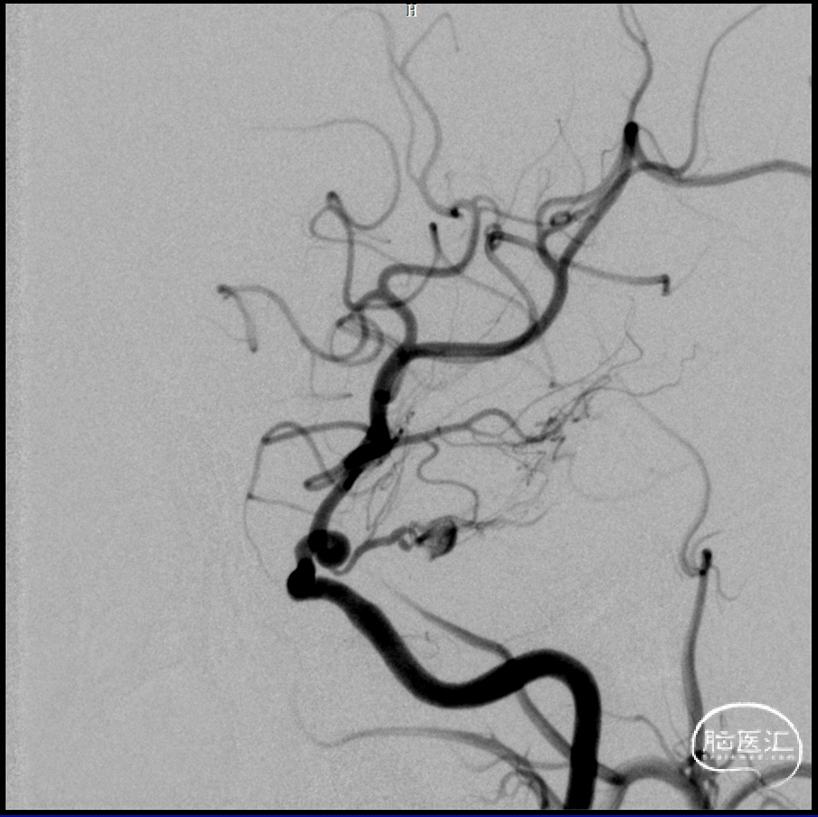

DSA

2023-08-30

前后循环3d融合寻找假性动脉瘤供血,

考虑为后交通动脉

1.右侧后交通动脉远端假性动脉瘤;

术后造影:假性动脉瘤消失